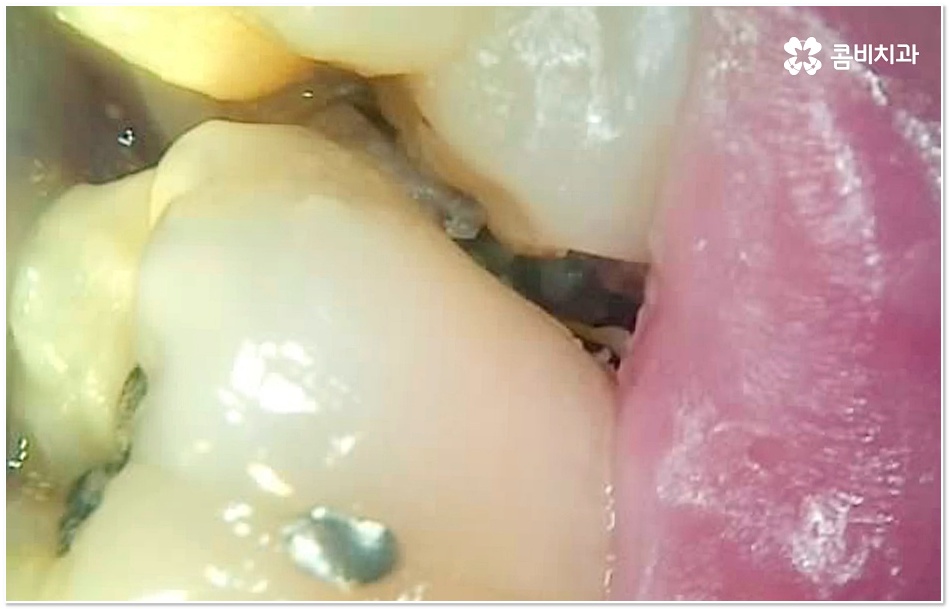

특히 그 중에서도 사랑니와 어금니 사이에 생긴 치아 사이 충치 는 구강 내 가장 안 쪽에 있기 때문에 제 때 발견하기도 어렵고 위치상 치료하기가 쉽지 않아서 병증의 진행 여부 및 상황에 따라 사랑니 뿐만 아니라 어금니까지 발치를 해야 하는 안타까운 상황에 이를 수도 있으니 그 전에 알맞은 대처를 해 주시는 것이 필요할 거예요.

충치는 입 안에 남아있는 음식물 찌꺼기 속 당분을 세균이 먹는 과정에서 배출되는 산으로 인해 치아가 부식되어 생기는 질환으로 보통 치아가 맞물리는 교합 부위인 치아의 윗면, 즉 저작면에만 충치가 생긴다고 생각하기 쉽지만 치아와 치아 사이에 생기게 되는 경우도 종종 있으며 특히 사랑니와 어금니 사이에 치아 사이 충치 가 생기면 말씀드린 것처럼 발견 및 치료가 굉장히 까다로워 질 수 있는데요.

사랑니 같은 경우는 영구치 중에서 가장 마지막에 자라기 때문에 다른 치아와 턱 뼈에 밀려 비좁은 공간에 누운 채 자리를 잡거나 부분적으로만 나오는 등 비정상적으로 맹출될 가능성이 높은 치아인데, 그렇지 않아도 위치상 관리가 잘 되지 않는 곳에서 앞 어금니와의 사이에 작은 틈새가 생기게 되면 음식물이 더욱 잘 끼고 빠지지 않으므로 치아 사이 충치 가 쉽게 발생하게 되는 거예요.

사랑니와 어금니 인접면에 치아 사이 충치 가 발생할 경우 육안으로도 보기 힘들 뿐 아니라 엑스레이를 찍었을 때에도 쉽게 발견하기 힘들 수 있기 때문에 초기에 알아차리지 못하고 치료 시기를 놓치는 경우가 종종 생기며 손상 정도가 많이 심각하거나 위치상 사랑니 발치 후에도 뿌리 끝 염증이 매우 심하거나 치아 사이 충치 로 손상이 심해 치료가 불가능한 케이스의 경우 불가피하게 어금니까지 발치를 해야 할 수 있으므로 이와 같은 상황에 이르지 않도록 평상시에 정기 검진을 꼬박꼬박 받아주는 것이 조기 대처 및 예방 등에 있어 여러 모로 유리하다고 할 수 있습니다.